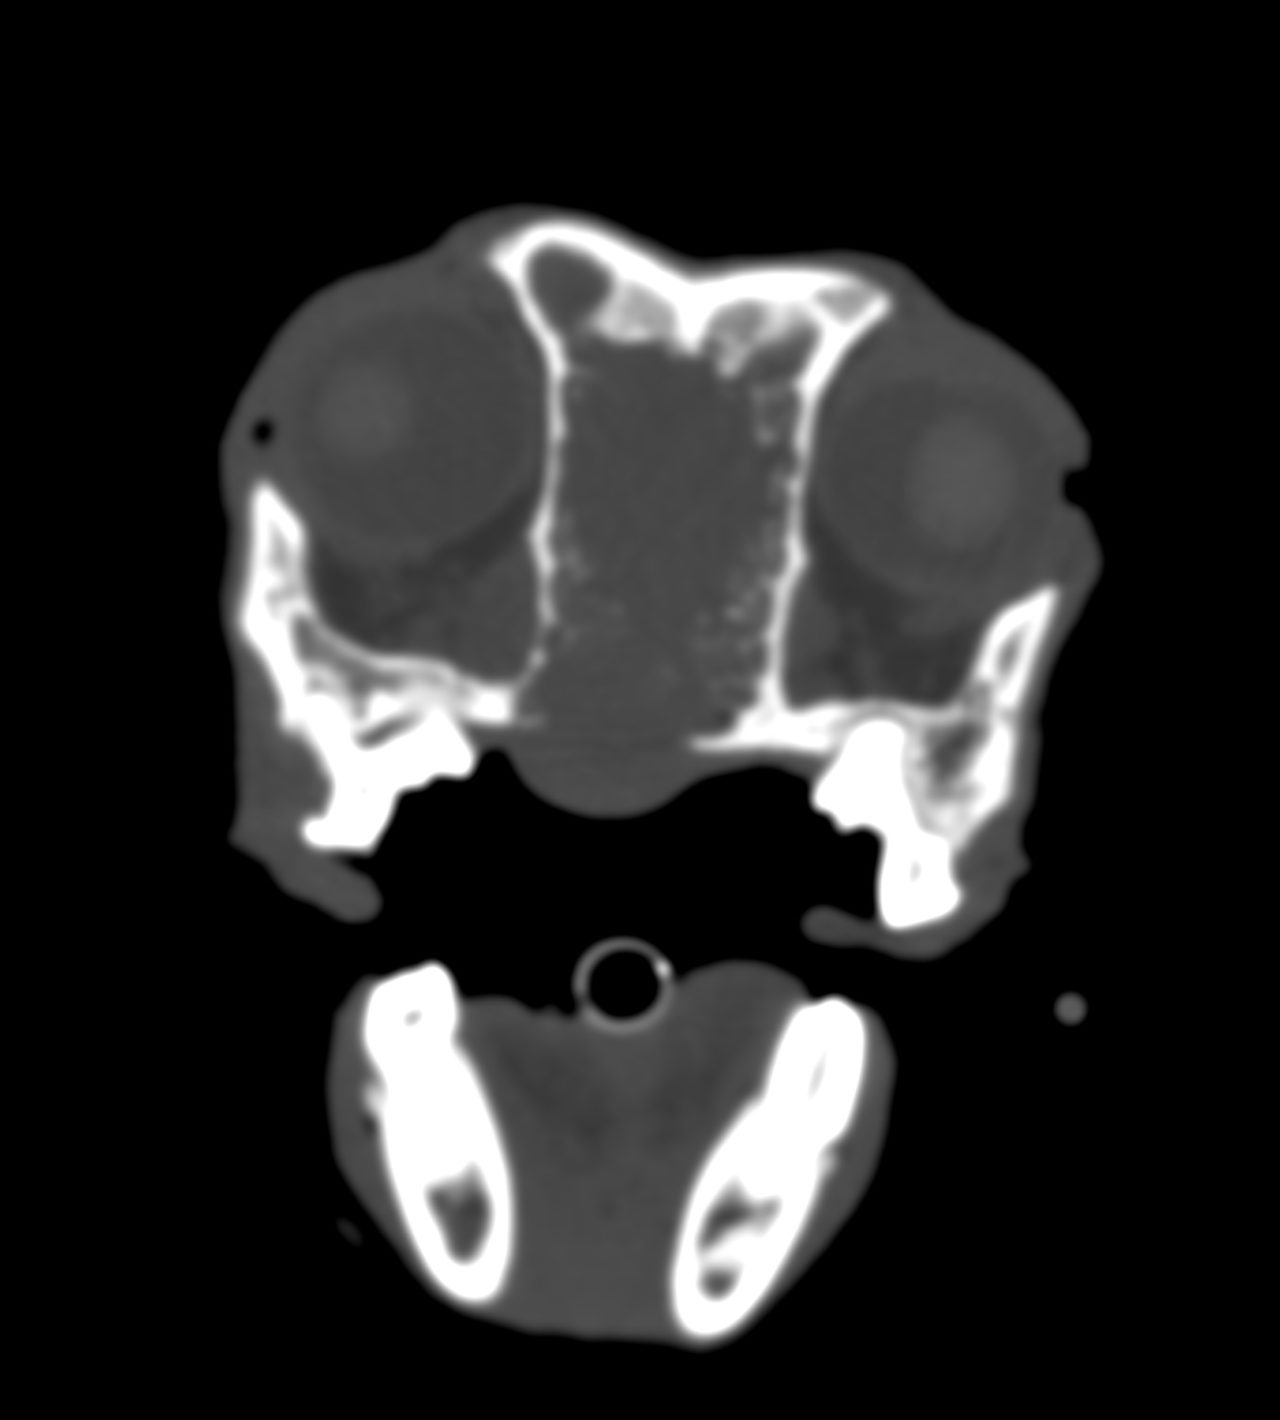

鼻腔内腺癌 慢性鼻炎がなかなか治らないとのこと、CTとバイオプシーで腺癌と診断された。 ブレオマイシンと放射線照射(オルソ)が行われた。 症例カテゴリー 放射線治療整形外科軟部組織外科脳神経外科内科腫瘍外科救急・集中治療リハビリテーション科腫瘍内科内視鏡科脳神経科呼吸器外科中医・漢方猫の腎移植循環器科